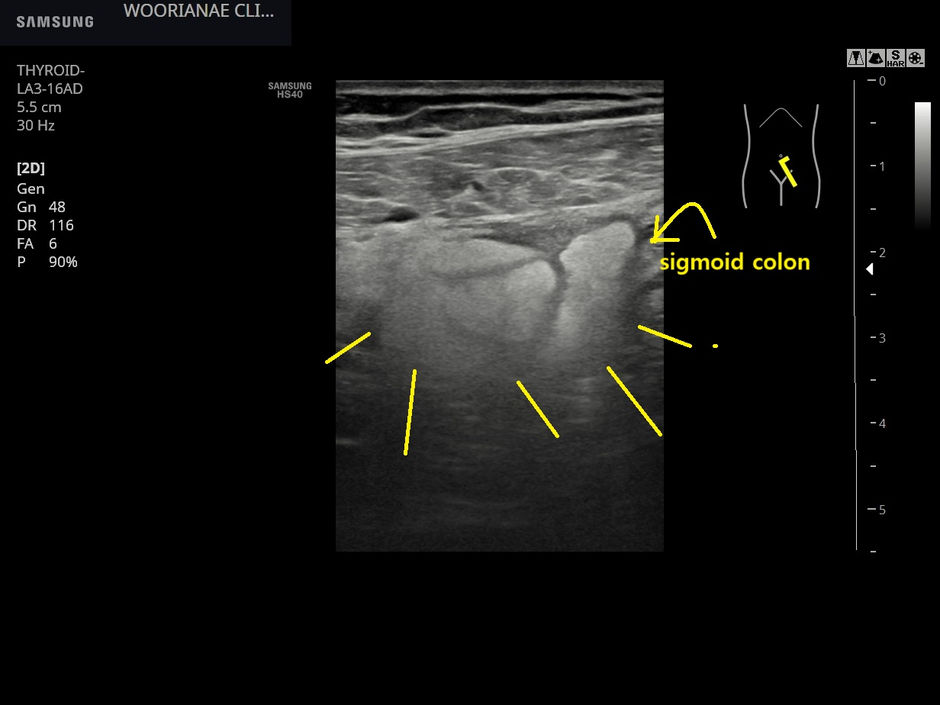

우상복부 통증/압통, 게실염을 의심하여 초음파로 힘들게 확인 - 동대문구 답십리, 전농동, 우리안애 우리안愛 내과

30대 중반 여자, 초진 갈비뼈 근처 통증으로 접수 ... 연골염인가 기대하면서 증상을 확인하는데 5일전부터 오른쪽 명치 아래? 힘줄때 딱딱해지는듯 아프다. 묵직한 느낌이 한번씩.. 수분씩 지속.. 하루 5회정도.. 2~3일전부터 애기 들고...